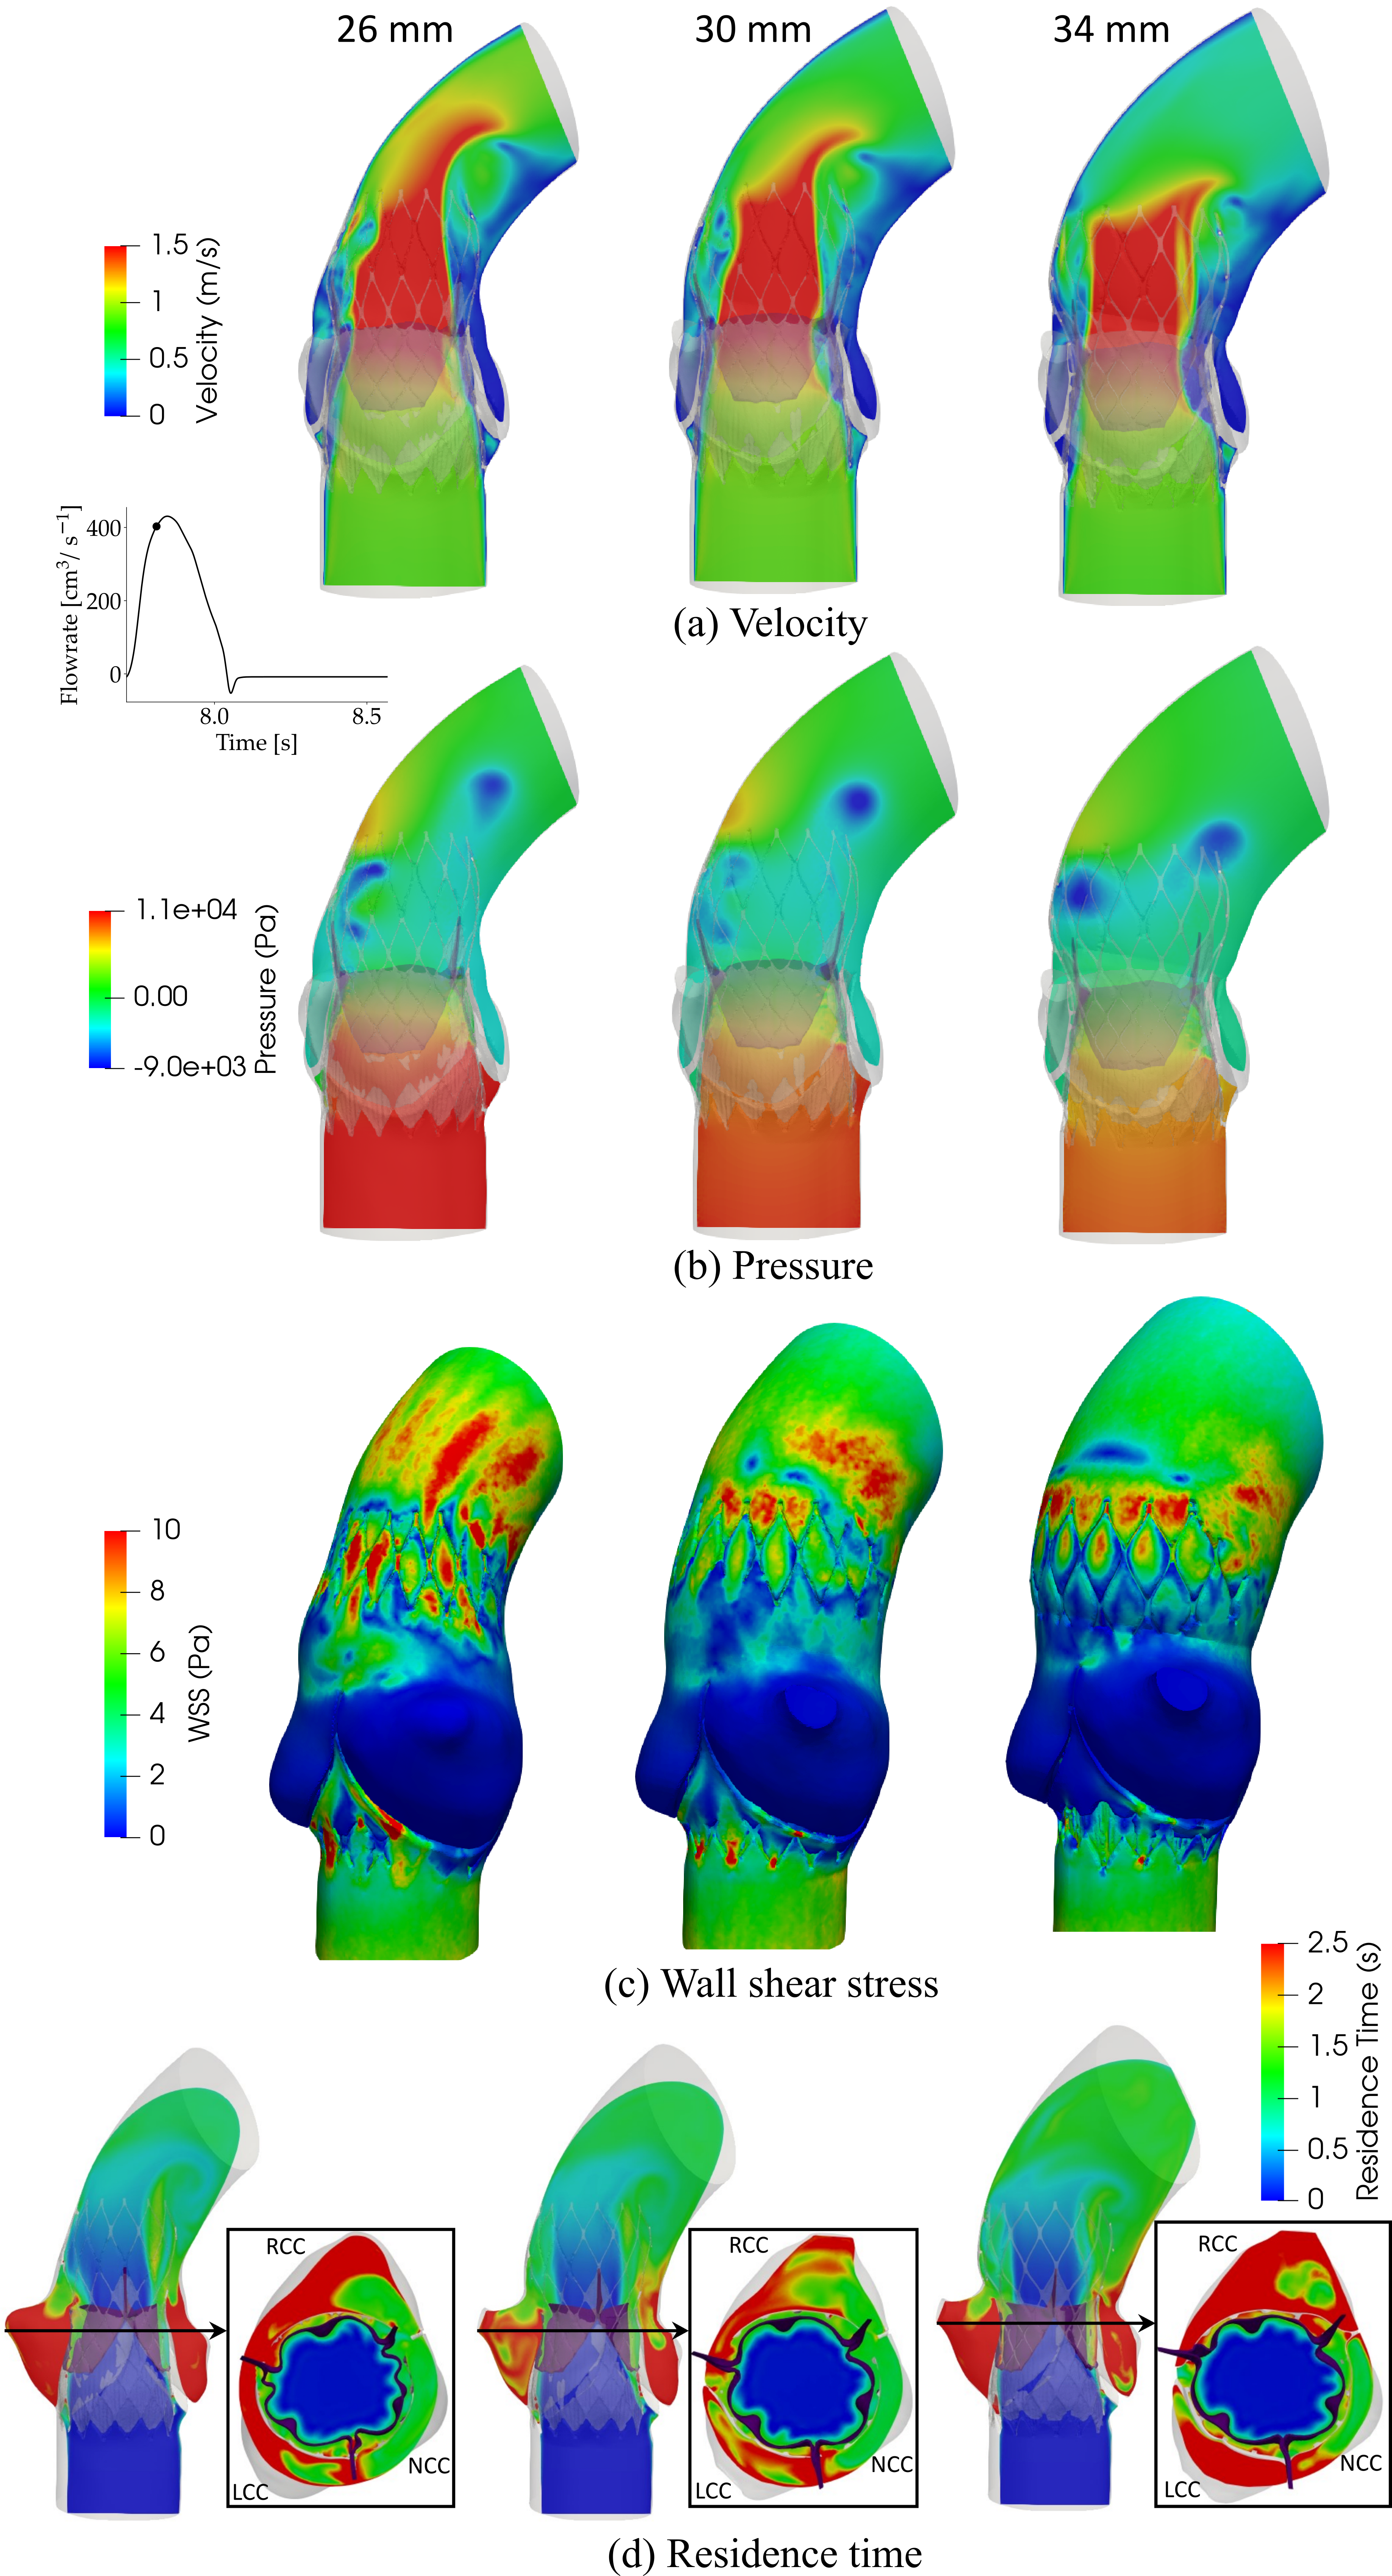

- In this study, we presented a comprehensive framework to analyze structural analysis of TAVR deployment, hemodynamic analysis via FSI simulation coupled with thrombogenic risk assessment via Lagrangian particle tracking.

Patient model reconstruction and TAVR deployment

Patient model reconstruction and TAVR deployment

Hemodynamic analysis

- A smaller STJ size impairs adequate expansion of the TAVR stent, which may lead to suboptimal hemodynamic performance.

- Larger STJ size marginally enhances the hemodynamic performance but increases the risk of TAVR leaflet thrombosis. Such analysis can aid pre-procedural planning and minimize the risk of TAVR leaflet thrombosis.